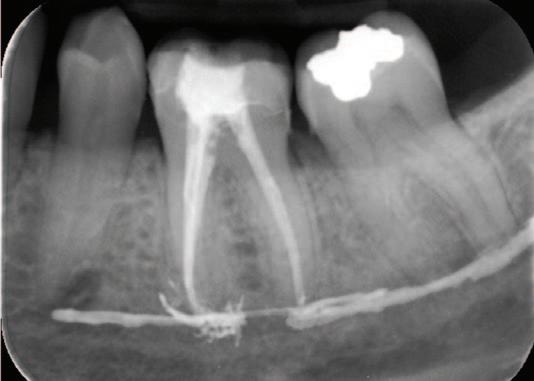

FIGURE 2: Left: Periapical radiograph pre endodontic treatment. Right: Post-endodontic treatment radiograph showing the presence of root canal filling material (AH Plus) inside the inferior alveolar canal.

Radiographic examinations consisted of digital orthopantomogram (OPG), peri-apical (PA), and cone beam computed tomography (CBCT) scans. The scans revealed that the lower left first molar root canals were obturated with a radiopaque material, and showed root canal filling extending beyond the apices of the tooth and approximately 5cm along the mandibular canal ( Figures 1 , 2 and 3 ).